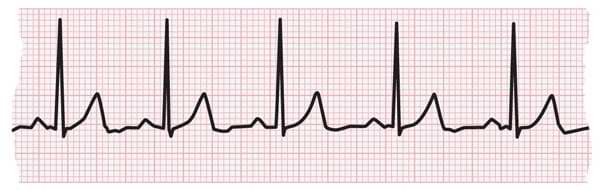

EKG strip showing a normal heartbeat